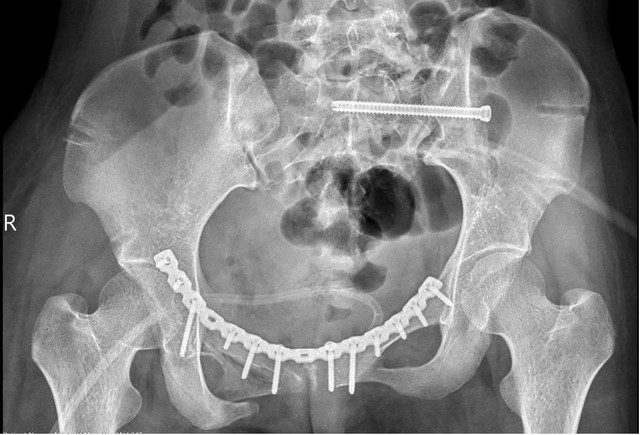

Sau 2 tuần điều trị tích cực, khi huyết động ổn định, bệnh nhân được tháo cố định ngoài và phẫu thuật lần hai để nắn chỉnh lại các di lệch (có sử dụng công nghệ in 3D giúp tiên lượng mức độ khó của phẫu thuật và chọn các nắn chỉnh khung chậu và vị trí đặt nẹp) kết hợp xương bằng nẹp vít bên trong, giúp cố định vững chắc khung chậu.

“Vì vậy, mục tiêu điều trị là phục hồi cấu trúc giải phẫu khung chậu và cố định vững chắc bằng nẹp vít, giúp bệnh nhân sớm vận động trở lại. Ở trường hợp này, khung chậu mất vững cả cung trước và sau, nên sau khi nắn chỉnh, chúng tôi cố định cung trước bằng nẹp vít và cung sau bằng vít xốp”, BS Khanh chia sẻ.